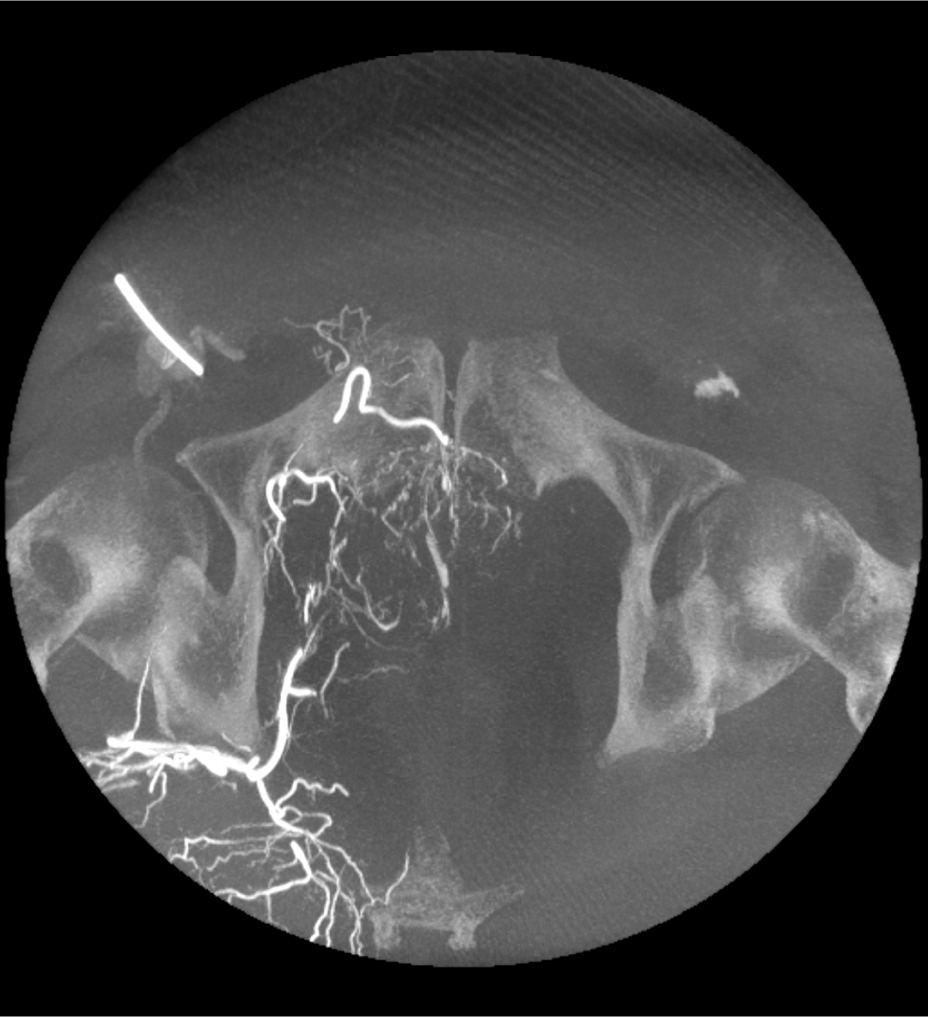

Mayor visualización con un software esencial para las aplicaciones clínicas avanzadas.